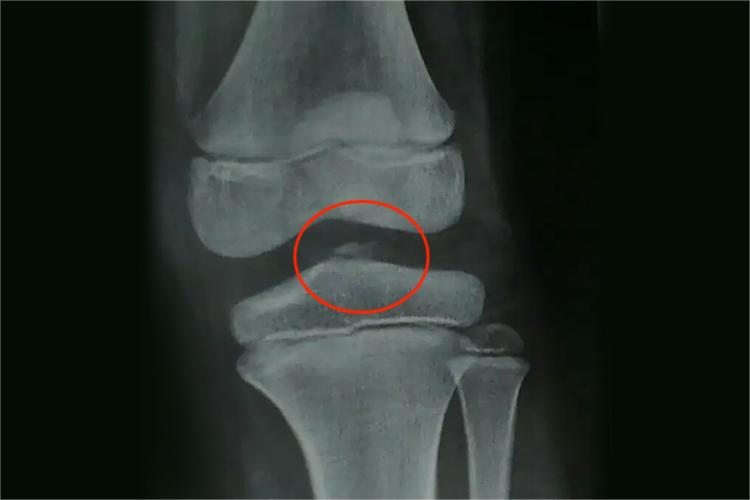

左胫骨髁间隆突骨折表现为左侧膝关节肿胀,以及骨的连续性中断,伴有疼痛等症状,由间接暴力导致,需遵医嘱治疗。

左胫骨髁间隆突骨折表现为左膝关节肿胀疼痛,活动受限,关节内瘀血,通过X线检查会发现骨的连续性中断,而且患者浮髌试验多呈阳性。此外,膝关节多有外翻或内翻畸形,表现为胫骨外髁、股骨外髁或内侧副韧带损伤,或胫骨内髁、股骨内髁及外侧副韧带损伤,或膝关节脱位的症状和体征。